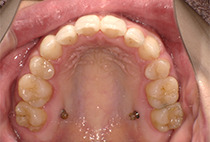

出っ歯と前歯のガタつきにお悩みだった20代女性の症例です。

矯正治療2年6ヶ月

インビザライン、インプラントアンカー、美容治療